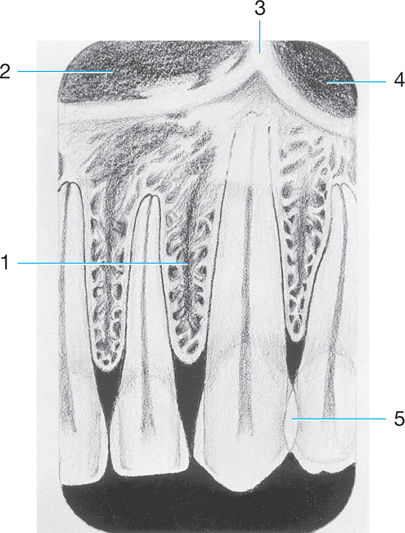

1.

PDL space

4

Identify the following: